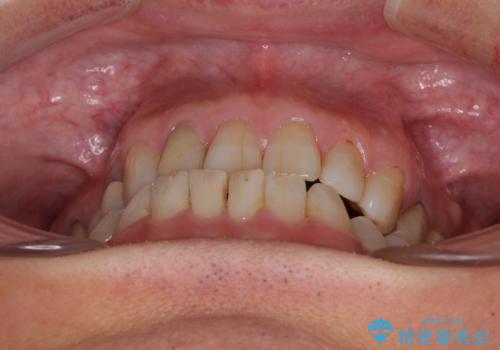

診察したところ、前歯は反対咬合であり、その影響で抜歯が必要な奥歯があることが分かりました。

抜歯が必要な奥歯は、インプラント並びにブリッジにより補綴を行い、上下前歯は反対咬合を改善させるように補綴治療を行うこととしました。

健全な歯を削ってセラミッククラウンに置き換えることは、本来避けるべき治療と考えますが、今回は①患者様が60歳を越えていること、②要改善の咬合により抜歯が必要な奥歯があること、③反対咬合の前歯改善の手段としてセラミック治療が選択肢にあることなどから、全顎的なセラミック治療を行うこととしました。